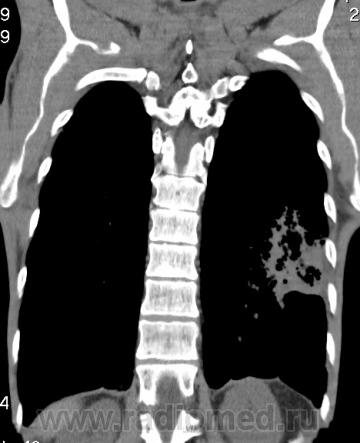

На фоне консолидации полость без содержимого. Может быть всё что угодно, что сопровождается деструкцией. Нужны ещё томограммы в лёгочном окне.

Изображения выставлены все. Ваше мнение уважаемые коллеги?

Туберкулёз.

Туберкулёз?

Это КТ 2-летней давности и попало оно мне в руки, после недавнего прохождения контроля пациентом, когда мы стали перед вопросом о специфическом / не специфическом процессе.

Тогда, пациента 2 месяца лечили от пневмонии, лечили интенсивности, стационарно, в серьёзном учреждении.

Предположу аспергиллез